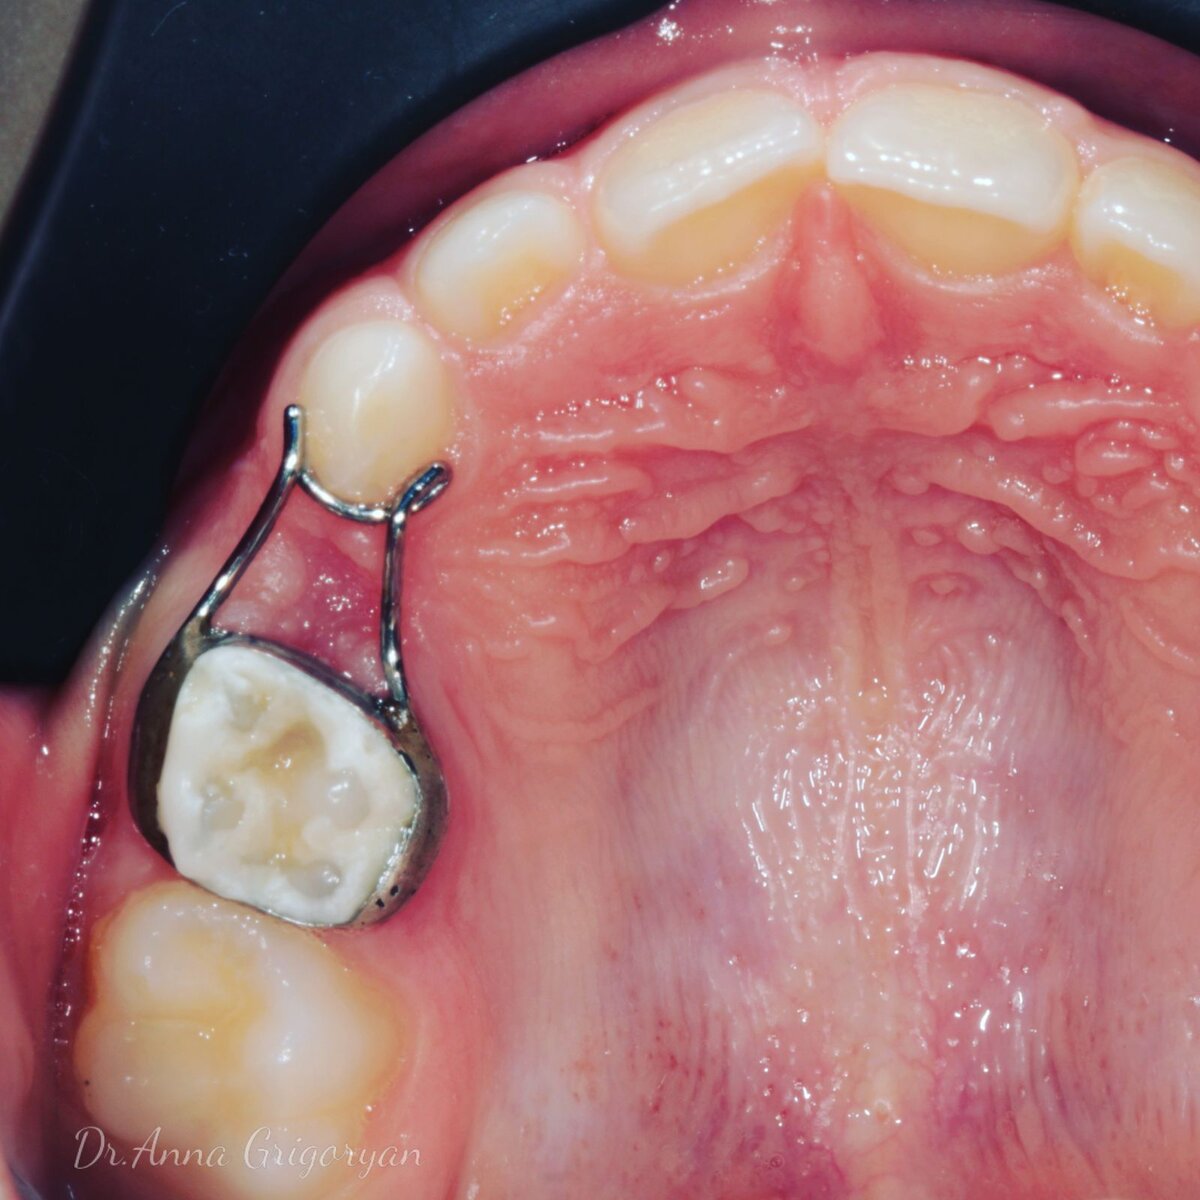

Самый часто используемый вариант для удержания места - это несъемный аппарат «кольцо-петля». Он состоит из назубного кольца на молочном или постоянном моляре и проволочной петли для сохранения про­странства. В идеальной ситуации петельная часть должна быть достаточно широкой для обеспечения проре­зывания постоянного премоляра без необходимости снятия аппа­рата.

Аппарат очень миниатюрный, несъемный, имеет простой дизайн, поэтому это идеальное приспособление для сохранения места.

Кольцо-петля